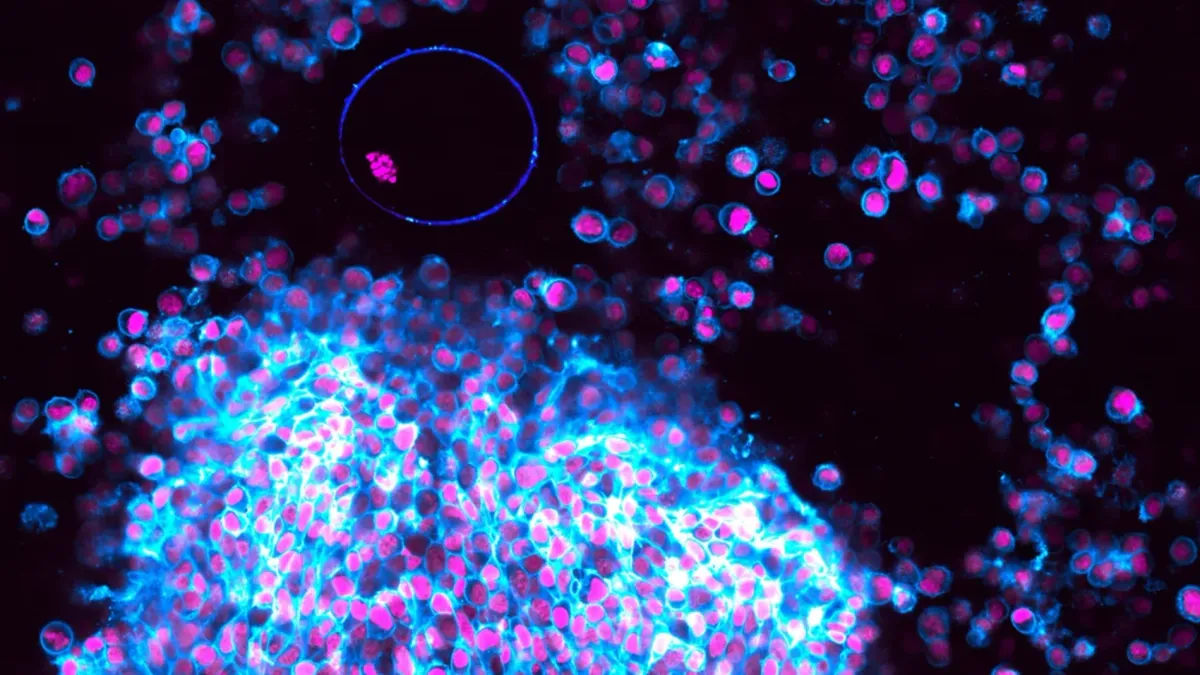

Onderzoekers van het Max Planck-Institut gebruikten een geavanceerde beeldvormingstechniek op follikels van muizen, die buiten het lichaam in een petrischaaltje groeiden. Ze werden gestimuleerd met specifieke hormonen die ovulatie in gang zetten. Met deze methode konden ze het ontstaan en de vrijlating van een eicel stap voor stap filmen, zoals nooit tevoren.

- Fase 1 – Groei van het follikel: Het meest rijpe follikel groeit binnen acht uur bijna twee keer zo groot. Dit komt door de productie van hyaluronzuur, dat zorgt voor instroom van vocht.

- Fase 2 – Samentrekking van de spierlaag: De buitenste spiercellen trekken samen en bereiden de ‘lancering’ van de eicel voor.

- Fase 3 – Vrijlating van de eicel: Uiteindelijk wordt de eicel krachtig naar buiten gestoten en komt in het laboratoriumschaaltje terecht. Precies deze fase is nu schitterend vastgelegd op video.